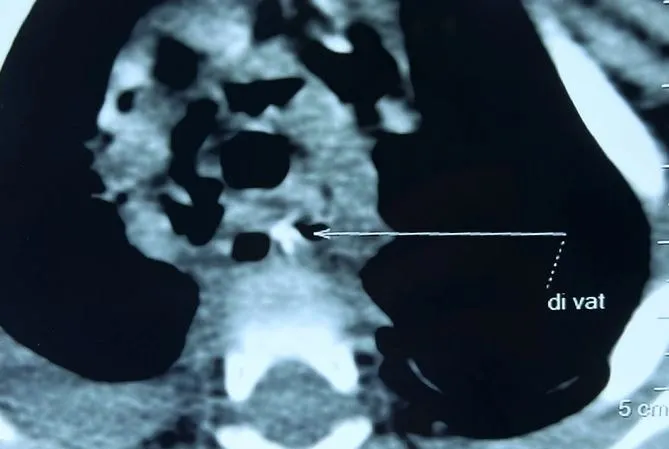

Kết quả chụp CT scan ngực cho thấy có khối áp xe vị trí nằm ngay phía sau tim, cạnh khí quản, thực quản và các mạch máu lớn. Được biết sau khi hội chẩn liên chuyên khoa, các bác sĩ nghi ngờ bé bị mắc dị vật.

Hình CT scan phát hiện dị vật trong người bé gái (Ảnh: BV).